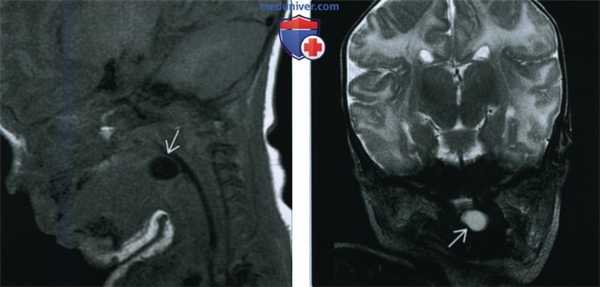

(Слева) На рентгенограмме в боковой проекции, выполненной ребенку со стридором, в проекции корня языка определяется тень с ровным краем, распространяющаяся в валлекулу, по интенсивности соответствующая мягким тканям.

(Справа) При аксиальной КТ с КУ в корне языка по средней линии визуализируется гиподенсная киста с ровными краями, не накапливающая контраст. На основании данных КТ образование нельзя достоверно дифференцировать с кистой щитоязычного протока, расположенной в области слепого отверстия.

(Слева) На МР Т1ВИ в сагиттальной проекции в корне языка визуализируется врожденная киста валлекулы с ровными краями, содержимое которой имеет сигнал, характерный для жидкости.

(Справа) На МР Т2ВИ в корональной проекции у этого же пациента в передних отделах ротоглотки визуализируется валлекулярная киста с неровным контуром и сигналом, типичным для жидкости.